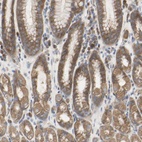

Immunohistochemical staining of human stomach shows moderate cytoplasmic positivity in glandular cells.